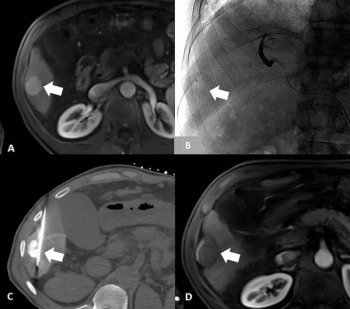

In a comparative study of staging systems for hepatocellular carcinoma, the Barcelona Clinic Liver Cancer (BCLC) system offered the highest likelihood ratio (LR) and lowest Akaike information criteria (AIC) for predicting overall survival after transarterial chemoembolization (TACE) for hepatocellular carcinoma.